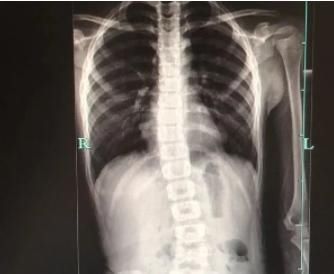

前几天,看到一个病例:一个8岁左右的孩子就发生了脊椎侧弯。

而且这样的病例,现在越来越多见。有的孩子是8岁,有的9岁,有的10岁,有的12岁。

甚至还有更小的。而且脊椎侧弯在初期非常隐匿,如果不注意,很难发现,当家长发现的时候,往往已经到了很严重了。而孩子之所以这么小就脊椎侧弯,和家长一些错误的养育观点和养育方式有关。很多孩子虽然在八九岁或者10岁以上才被发现脊椎侧弯,但实际上祸根在很小的时候就已埋下。今天我们就把容易导致孩子脊椎侧弯的常见原因和大家说清楚,希望这样的错误,大家都能避免。脊椎侧弯的危害,孩子越大,会越严重孩子脊柱侧弯的危害是很大的。不仅影响体态和姿势,而且对健康、生活劳动、学习和社会交往带来直接影响。严重脊柱侧弯给孩子增加沉重的心理压力和精神负担.脊椎侧弯可造成胸廓畸形,使胸腔容量减少,胸廓的活动度也相应减小;脊柱侧弯的凸侧肺组织严重受压,肺发育不完全,肺活量小,甚至肺不张,进而影响心功能。更严重者,脊柱侧弯畸形可引起脊髓与神经根的受压。神经根受压会引起相应神经根支配区域的麻痹或放射性疼痛;脊髓受压严重者可引起瘫痪。